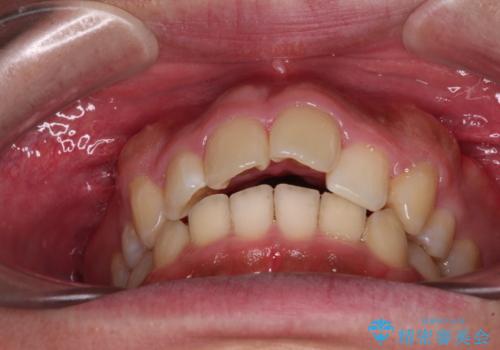

- 学生時代に抜歯矯正した歯列が後戻りしてきたとのことで来院された患者様です。

舌の突出癖が原因で上顎前歯が前方に移動したと考えられたため、舌のトレーニングを徹底して行っていただきながら、後戻りを解消していくこととしました。

マウスピース矯正でもワイヤー矯正でも対応可能でしたが、患者様の希望によりワイヤー装置による矯正治療を行うこととしました。

ワイヤー矯正ということで、上顎大臼歯を後方に移動するための補助装置を併用して、積極的に前歯を引っ込めていくこととしました。

上顎歯列全体がスムーズに後方移動でき、1年で治療を終えることができました。